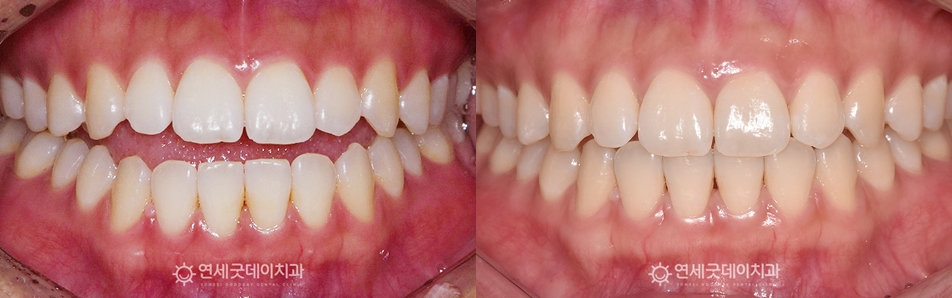

상하악의 공간이 줄어들며 개방교합이 완전히 해소되었고, 환자분은 심미적 목적 보다도 ▲ 개방교합 교정 전후비교 안타깝게도 개방교합은 재발 가능성이 높은 형태로 이에 연세굿데이에서는 개방교합 케이스에 한해 긴 치료 받으시느라 고생 많으셨습니다 :) |